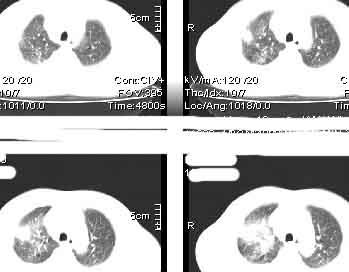

该病例我的诊断意见:右肺上叶周围型肺癌伴纵隔和右肺门淋巴结增大和右肺上叶阻塞性肺炎{病灶周围致密影以近肺门侧明显!}。右侧少量胸腔积液。

一. 1)症状有无发热及慢性过程.2)化验室检查?3)有无tb接触史?二.右肺上叶见片团状影,边界欠清,外侧方见一结节状软组织影,密度欠均匀,内可见低密度坏死区.周围强化明显,肺内见纤维索条影,局部胸膜增厚,但无明确胸膜凹陷.上叶支气管壁增厚,肺门及纵隔淋巴结增大.右侧胸腔少量积液.诊断意见:1右肺上叶慢性感染性疾病(肺tb?)伴肺门,纵隔淋巴结大.右胸少量积液.右肺上叶结节影多为tb球?2右肺上叶周围型肺ca伴肺门,纵隔淋巴结转移待排.右肺上叶炎变(肺门及纵隔淋巴结压迫).右胸少量积液.等待随返结果.